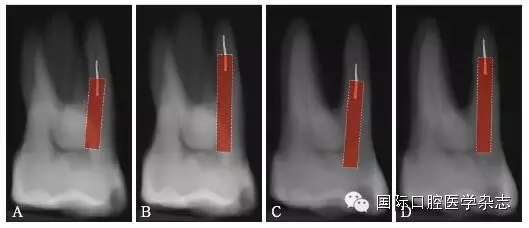

3.2.5 取出難度評估 多數(shù)情況下,如果分離器械上1/3能夠暴露,通常能夠取出。位于直根管、近根管口的分離器械較位于彎曲根管的器械容易取出。位于根管通暢部分的分離器械通??梢匀〕?。如果分離器械位于根管彎曲附近,并且牙本質(zhì)厚度容許建立從根管口到器械冠方的通道以接近其冠部末端,而不至于產(chǎn)生穿孔等并發(fā)癥,則仍有可能將其取出。在這些病例中,都必須建立到達(dá)分離器械上部的直線通路。如果器械分離于彎曲根管的根尖部,則很難建立安全的通道,且分離器械移動(dòng)可能造成器械超出根尖孔,風(fēng)險(xiǎn)較大,通常不太可能將其去除(圖8)。

A:分離器械位于較直的根管中上部分,較容易取出;B~D:分離器械位于根管彎曲之下或彎曲根管近根尖部,無法取出。

圖 8 取出難度的評估